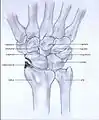

Post-traumatic osteoarthritis can be classified into four stages.[1][6] These stages are similar between SLAC and SNAC wrists. Each stage has a different treatment.

- Stage I: the osteoarthritis is only localized in the distal scaphoid and radial styloid.

- Stage II: the osteoarthritis is localized in the entire radioscaphoid joint.

- Stage III: the osteoarthritis is localized in the entire radioscaphoid joint with involvement of the capitolunate joint.

- Stage IV: the osteoarthritis is located in the entire radiocarpal joint and in the intercarpal joints. It also may involve the distal radio-ulnar joint (DRUJ).

Stage I